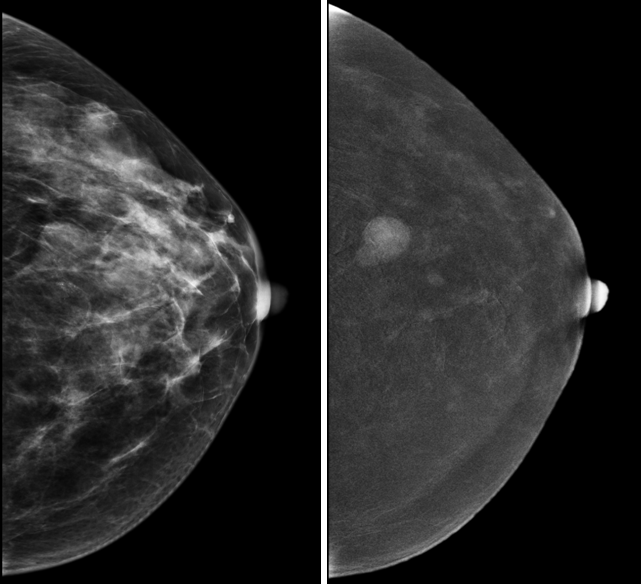

Маммография (МГ) – это рентгенологическое исследование молочных желез. Любой рентгенологический метод подразумевает лучевую нагрузку или облучение исследуемого органа. Но так ли это страшно? Согласно последним исследованиям, при выполнении цифровой МГ вы получаете такую же лучевую нагрузку как при полете на самолете. Но ценность МГ гораздо выше, ведь вовремя выполненное исследование может спасти жизнь! Тем более что выполнять МГ женщинам после 40 лет рекомендуется раз в два года.

Аналоговая МГ — когда после проведения исследования врач анализирует пленочные изображения. Данный вид маммограммы, если выполнен правильно, решает главную задачу – позволяет определить патологию молочных желез, особенно у женщин с типом строения А и В. Но у данного вида МГ отсутствует возможность редактирования или так называемой цифровой обработки изображений, что возможно только с цифровой МГ.

Цифровая МГ позволяет врачу увеличивать изображение, менять контрастность и яркость, что, несомненно, помогает увидеть больше изменений на снимках. Также цифровые изображения можно архивировать, пересылать между учреждениями, городами и даже странами, а также копировать на диск. Своих пациенток я прошу приносить маммограммы, записанные на диске, так гораздо удобнее работать, и у меня есть возможность получить больше информации, чем если на консультацию принесут пленки.

Рис.1 Маммография, выполненная в двух проекциях: фиброаденома левой молочной железы

Рис.2 Маммография, выполненная в двух проекциях: рак правой молочной железы